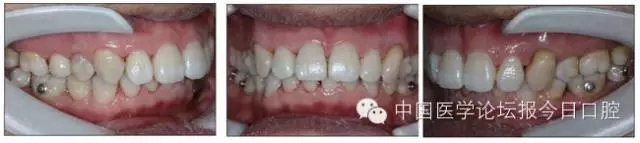

口內(nèi)情況:恒牙列,24、34、44缺失,磨牙Ⅲ類關(guān)系,上牙列散隙,上前牙扇形漂移。前牙深覆(牙合)、深覆蓋??谇恍l(wèi)生較差,11與12間牙齦乳頭紅腫,多個(gè)牙探診有牙周袋形成,11松動(dòng)Ⅰ度,余切牙松動(dòng)(-),患者面像及口內(nèi)像如圖1、2所示。

圖2 治療前口內(nèi)像